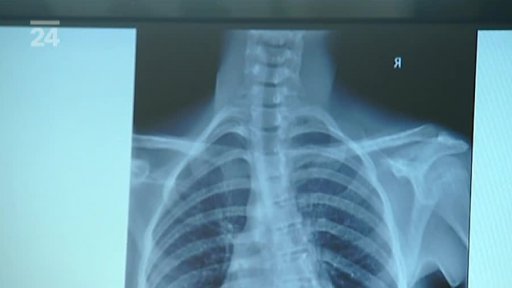

Unikátní operace skoliózy: ortopedi Fakultní nemocnice v Brně-Bohunicích využili v rámci mezinárodní studie americké implantáty. Speciální tyče umožňují páteř dokonale srovnat a mají řadu dalších výhod. Lékaři mluví dokonce o převratu v léčbě skoliózy a Česká televize měla jako jediná možnost operaci natočit. Stejně jako příběhy Báry a Štěpánky, které zákrok podstoupily a zařadily se tak mezi 20 pacientů na světě.